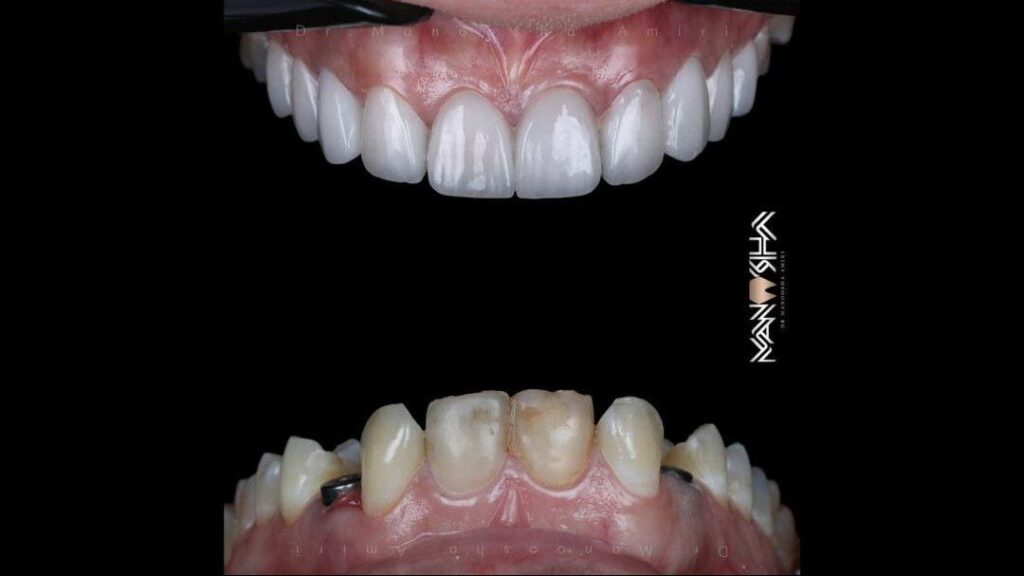

دندانپزشک متخصص – ترمیمی و زیبایی